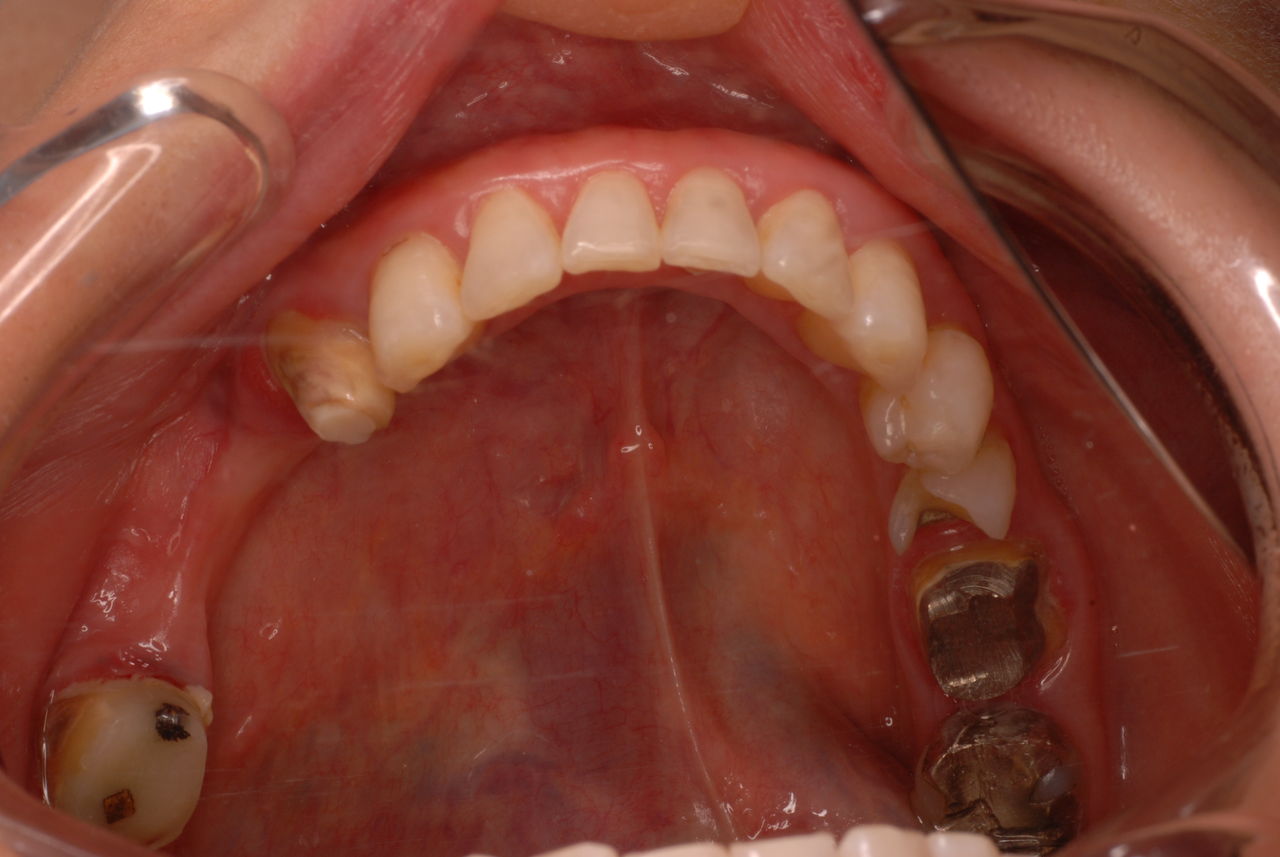

今日のすべての患者さんは、一人を除いて新患を含めてすべて歯周病の方でした。

歯周病は殆どの方に存在し、気づかないうちに進行していきます。

そして場所や痛みなどの症状がはっきりしないのです。冷たい水がしみることもあります。

なかなかブラシの使い方ができていないようで、歯磨きと歯周病でのブラシの使い方は別なのですが、習ったことも検査もされずに金属を被せたりしているようで、これからも歯医者さんで抜かれたり、その後にインプラントのような高価な“クギ”を打ち込まれる方が増えるかと思うと残念です。

まず検査をして、ブラシの使い方を習得して歯医者さんで削ったり抜かれたりしないように予防に注意する方々が増えないかと思う日々です。

被せても、詰めても病気は治らないのですから。又病気の元になり易い不適合な差し歯や金属、インプラントがあればそこからバイキンが侵入して体に悪さもしやすいのではないかと心配しています。

全身にバイキンが周り病気の原因になるというのに気づかない方が多いのです。